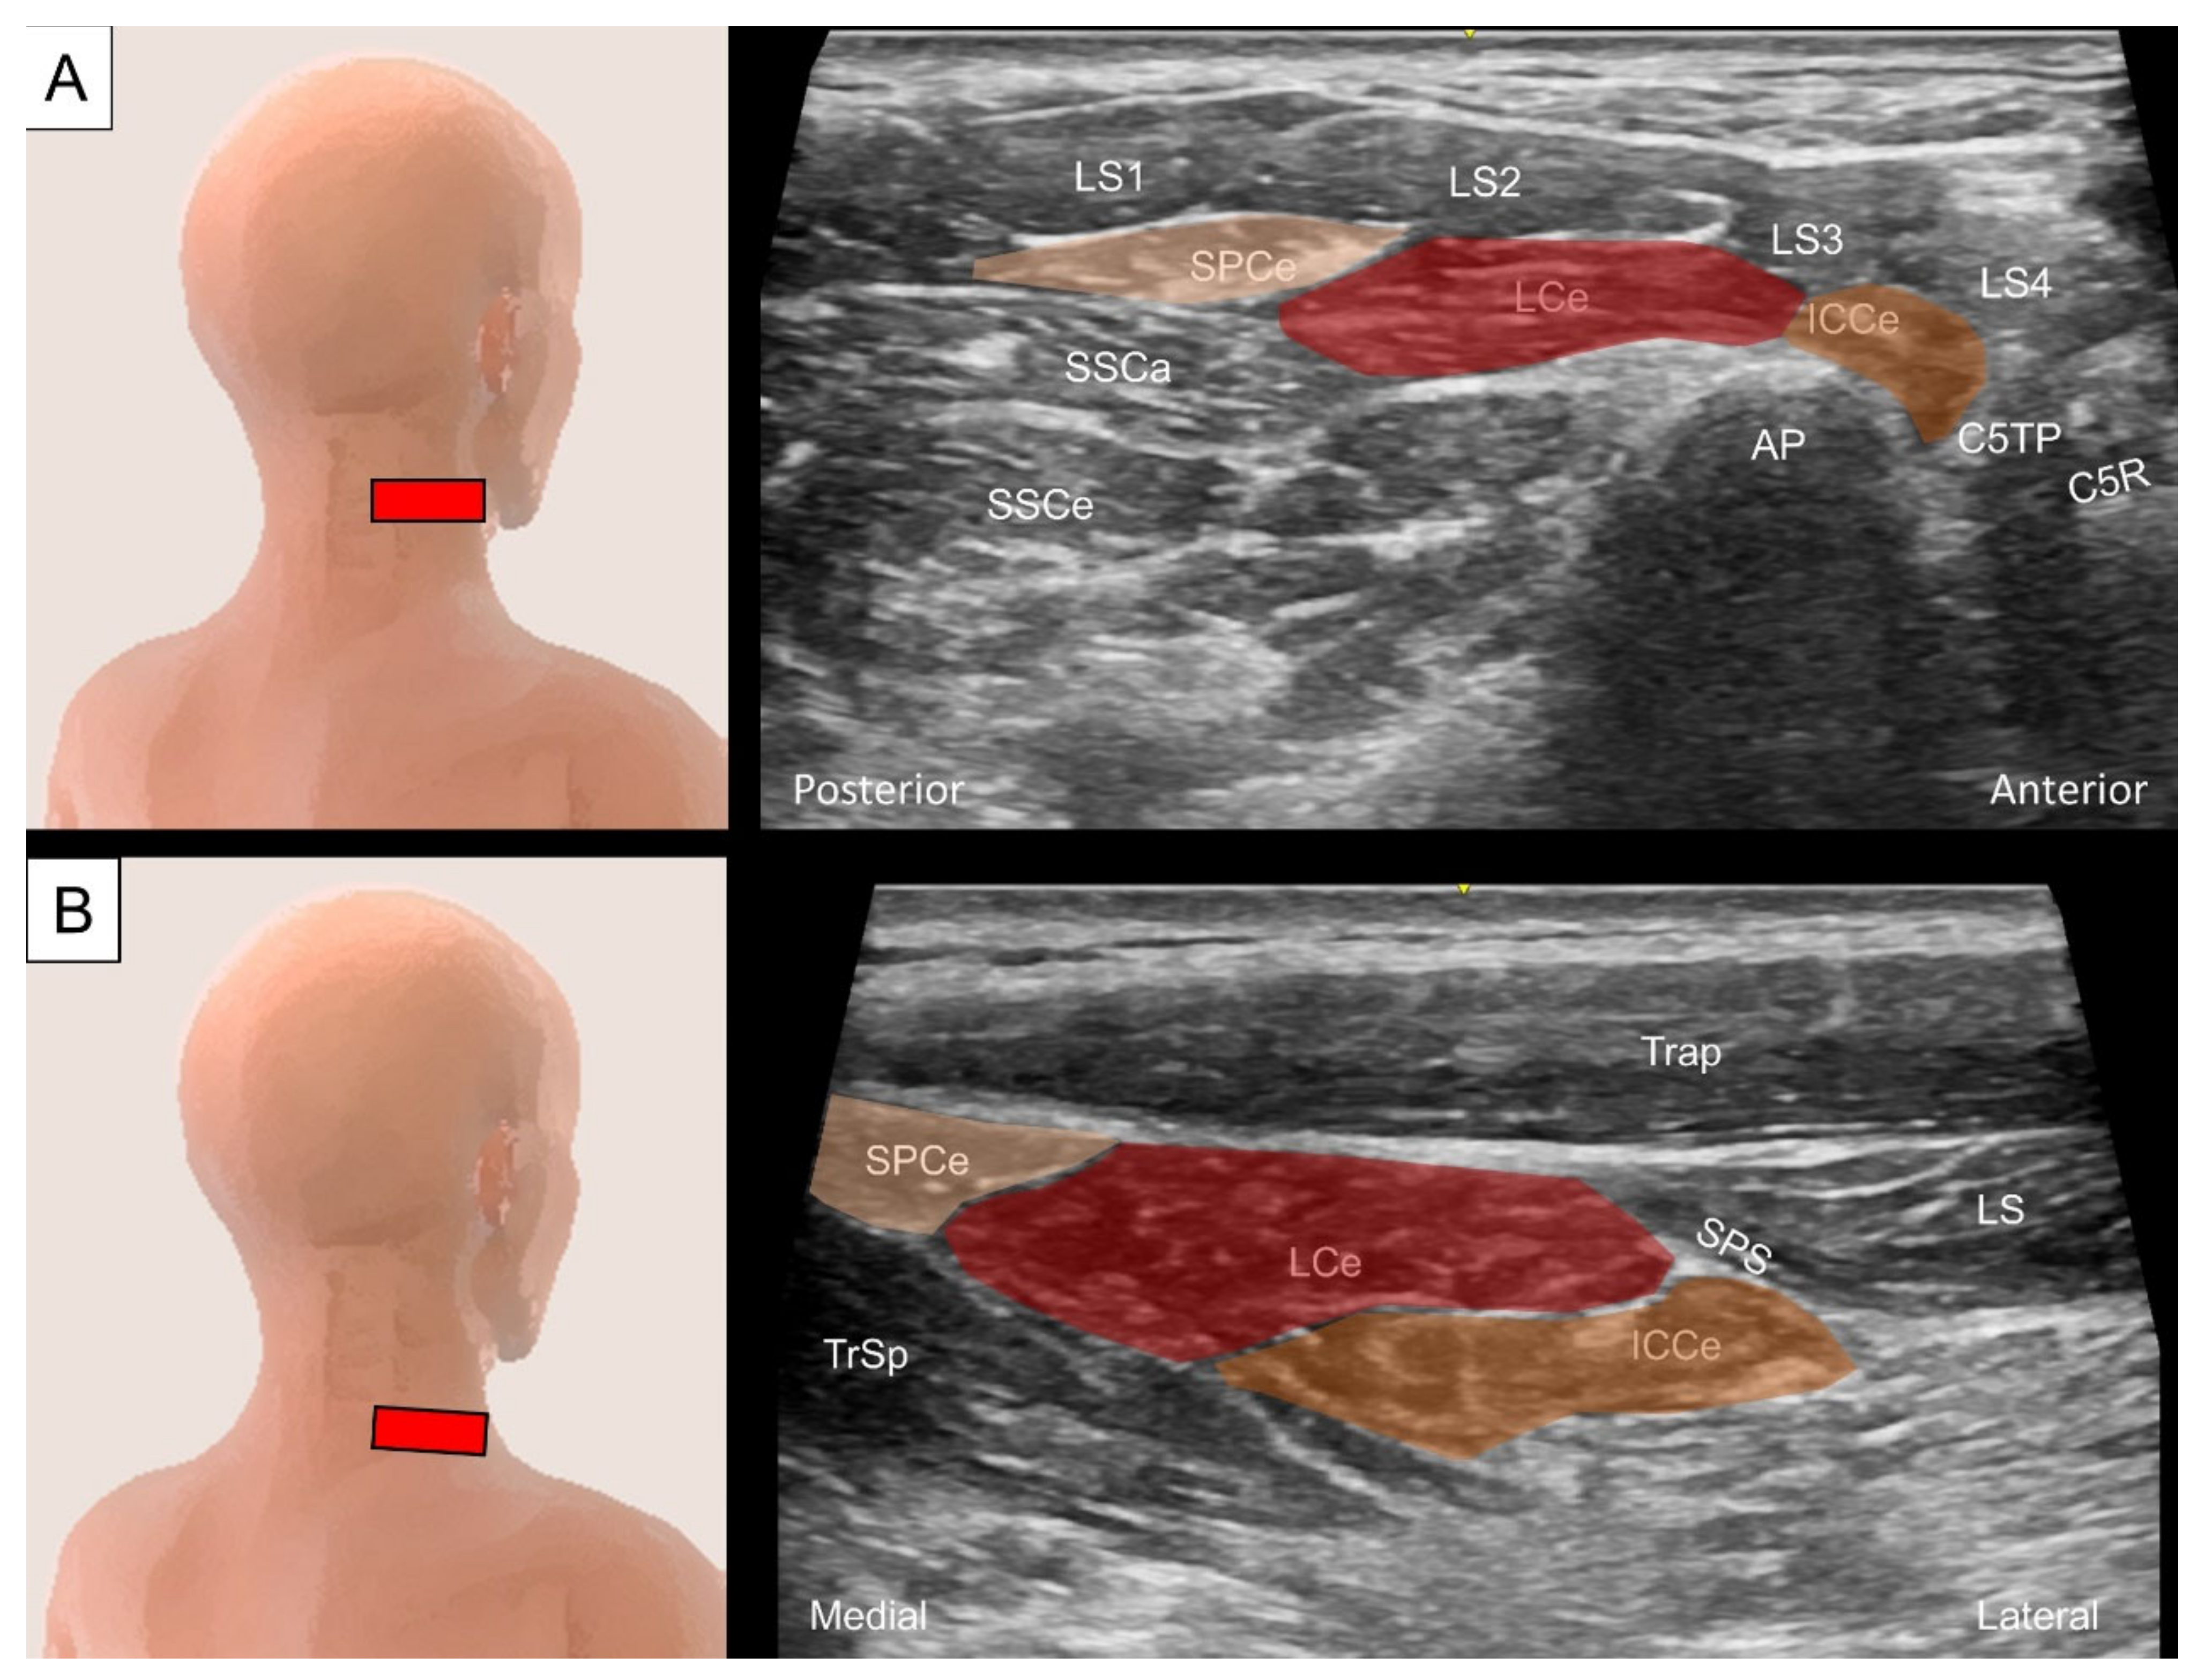

4.2. Iliocostalis/Longissimus/Splenius Cervicis

4.2.1. Anatomy

4.2.2. Sonographic Scanning

4.2.3. Clinical Relevance